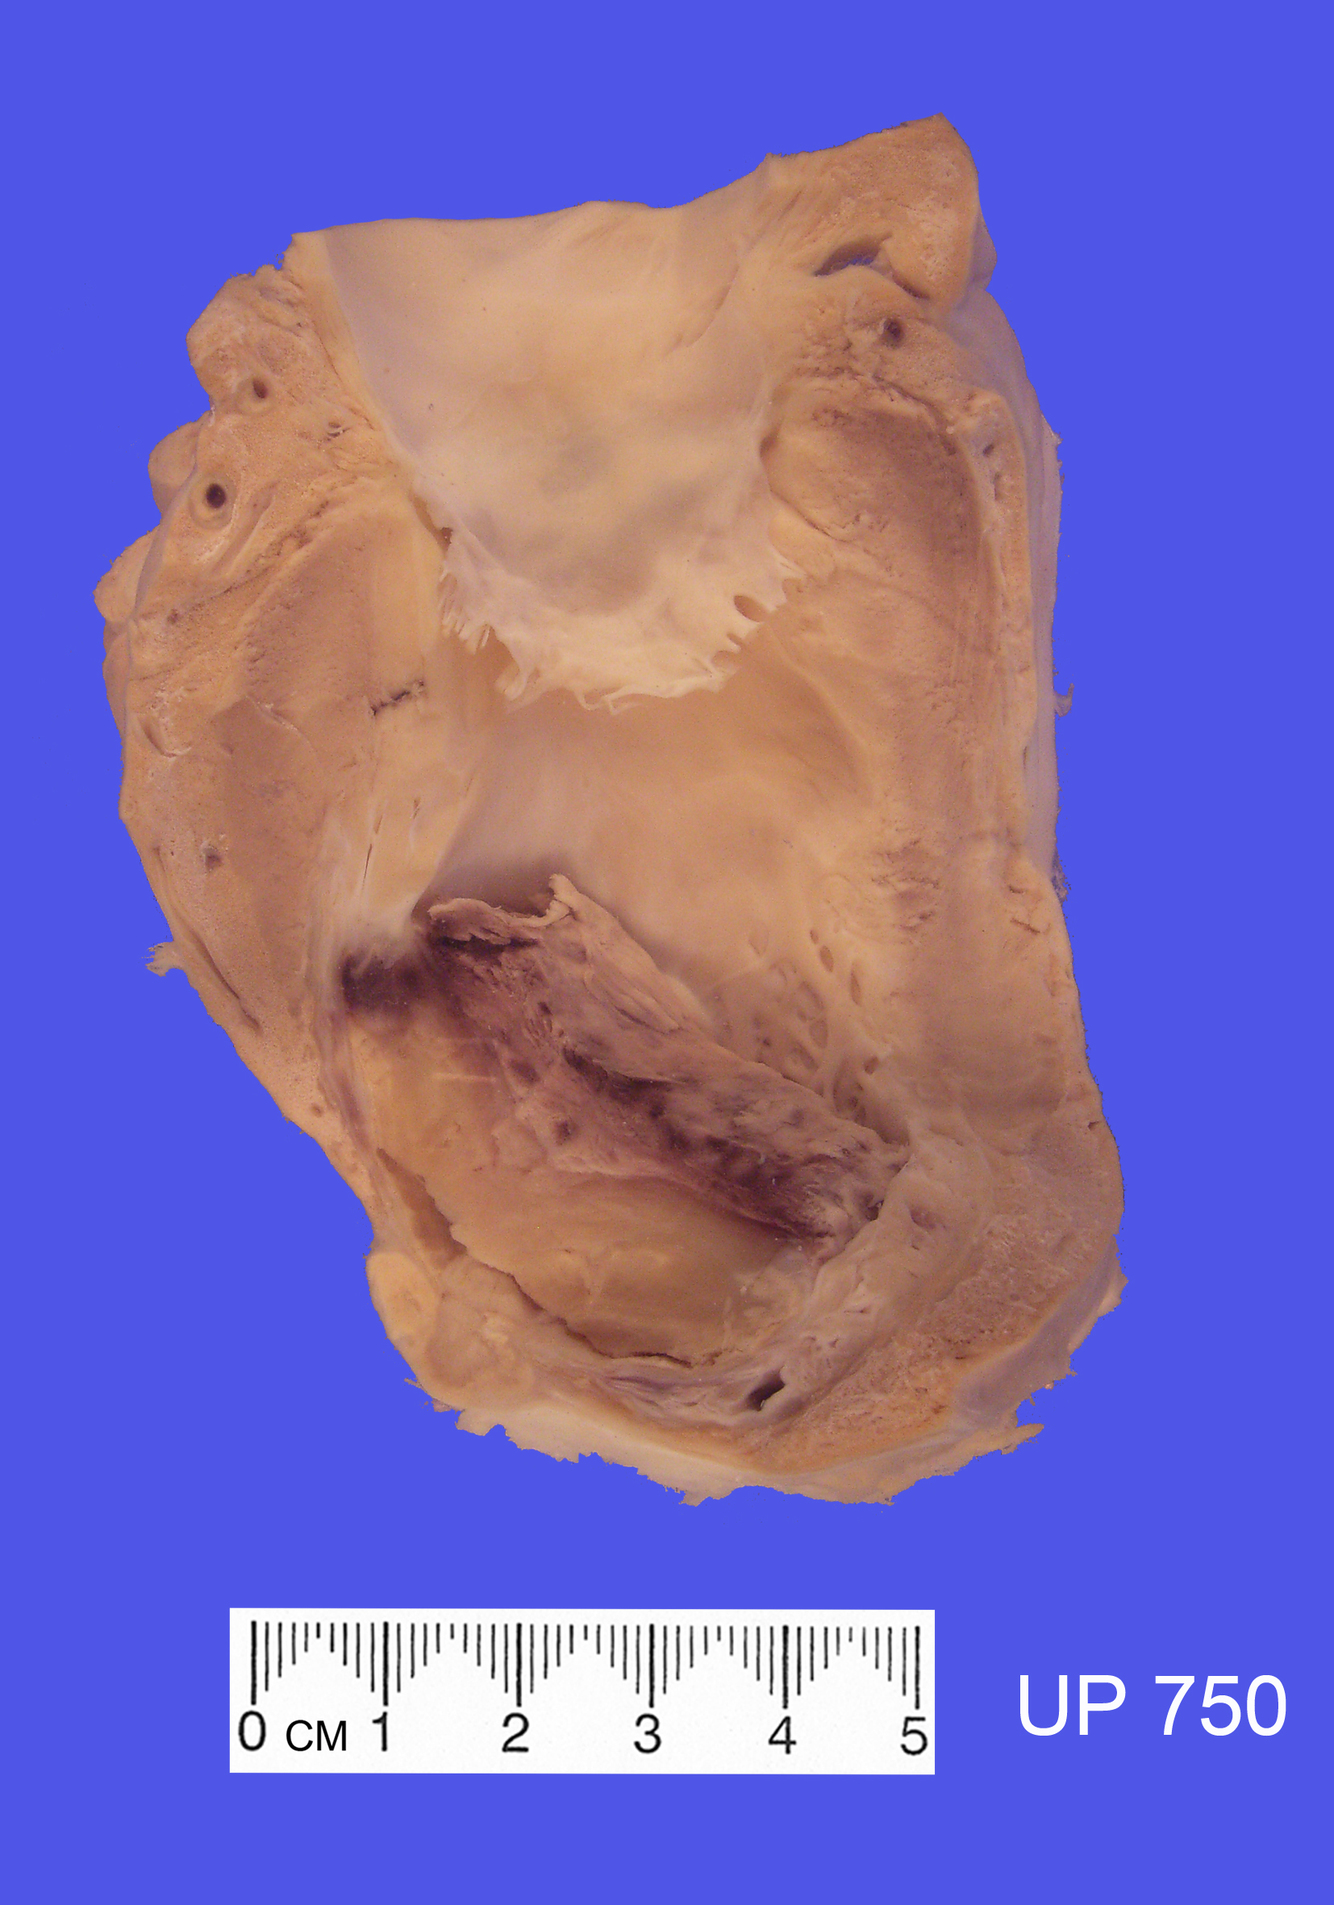

The specimen shows a large infarct of the myocardium involving the apex, the lateral and posterior walls of the left ventricle and much of the interventricular septum. This is the distribution of the left anterior descending coronary artery.

There is a pericarditis overlying the infarct and the infarct is seen as an irregular, transmural, yellow necrotic zone surrounded by a hyperaemic margin.

There is severe coronary artery stenosis as a result of atherosclerosis.